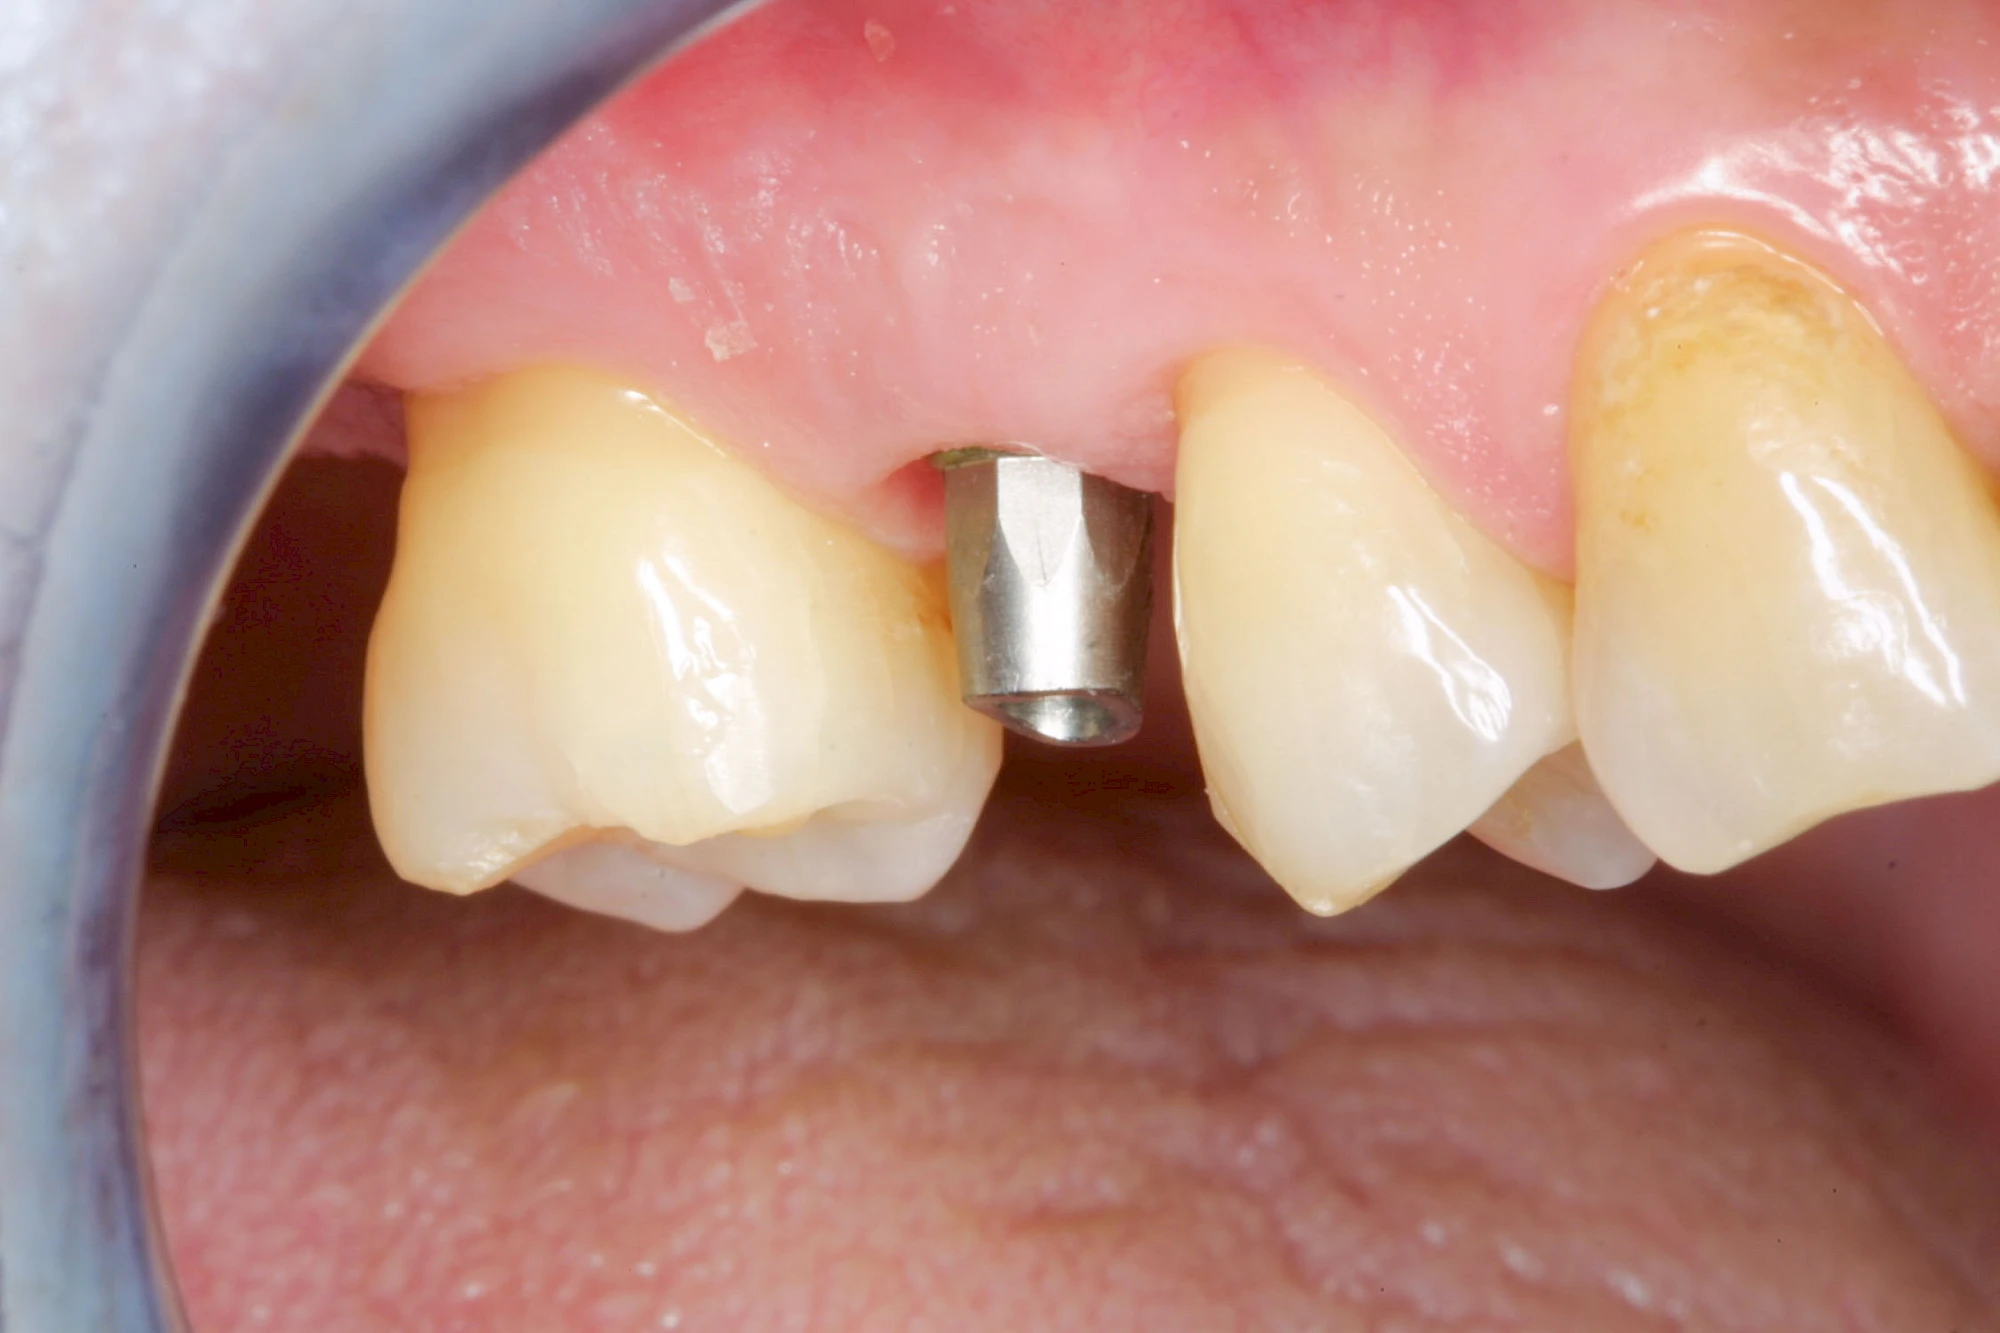

Implantate sind künstliche Zahnwurzeln. Nach einer gewissen Einheilzeit im Knochen (meist 3-6 Monate) erfolgt über einen separaten Aufbau (Abutment) die Befestigung einer Krone bzw. Brücke oder Zahnprothese.

In seltenen Fällen sind Implantate samt Aufbau aus einem Stück gefertigt. Auch gibt es Situationen, die ein Früh- oder sogar eine Sofortbelastung erlauben – dann kann die Einheilzeit der Implantate in den Knochen verkürzt oder sogar gänzlich darauf verzichtet werden.